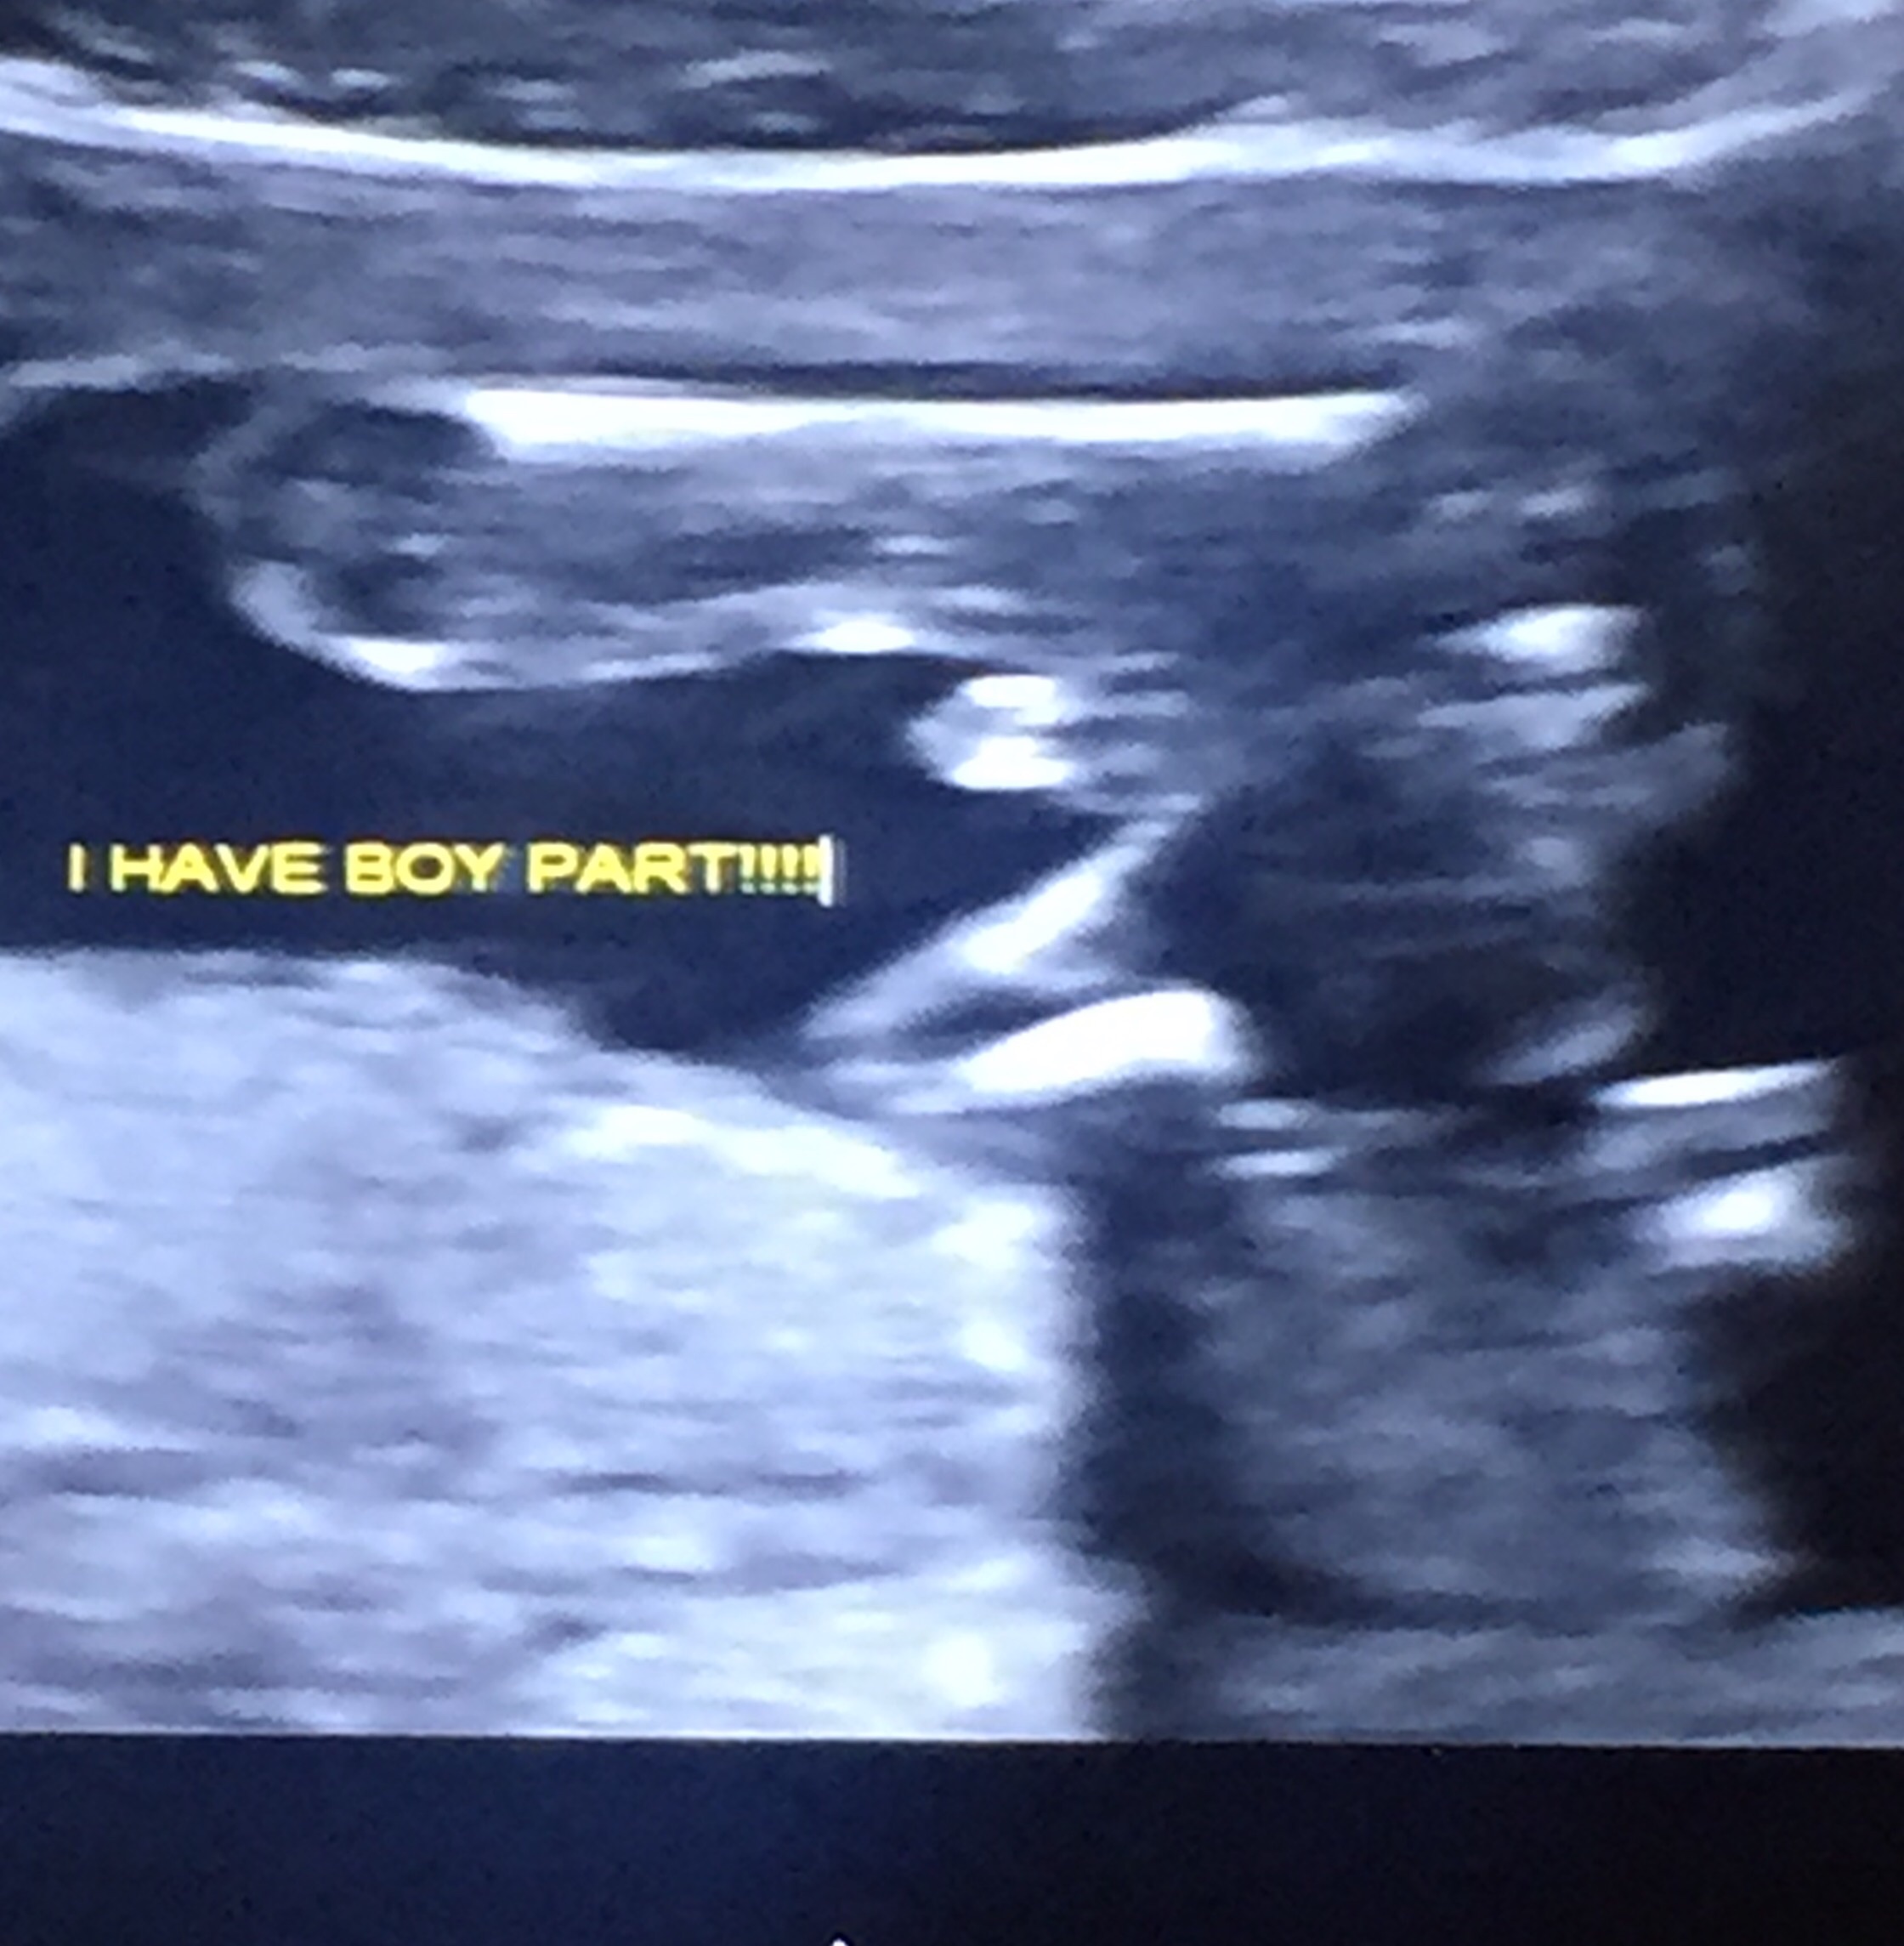

We found out today we are having a bouncing baby boy! Unfortunately I won't know if he's healthy until the doctor calls me later today or tomorrow because she was rushed into delivery. I have heard horror stories about mommies finding out they are really having girls in the delivery room so now it's stuck in my head. Opinions??? The tech seemed VERY convinced he is a he but I need an extra push.

• I would be unsure by that picture too. Don't let other posters bring you down. I am having 2 boys and good gracious if that really is his "boy parts" (as my ultrasound has it written) then he is well endowed ;). I haven't tried to post a pic but let me see if I can. I guess my phone won't let me right now

• Exactly! I mean I'm sure she's zoomed in to a degree and she did say he was peeling but oh my god...

• This is entirely a guess, but that looks like an umbilical cord to me. Just by the shape and position. Again, guessing here... I'm sure your tech saw definitive proof if they said that!

• Today my tech told me that girls have 3 lines and boys have "turtles." That appears to be a boy to me, but I'm not a professional.

• I would trust your tech. This is one of the many things they are trained for. I am having a boy and the picture I was given is very similar to what you have. The picture is zoomed in and will look bigger then it actually is especially since baby is still pretty tiny (a pound or less). My little guy was only 11 ounces at the time of my ultrasound yet looks huge in most pictures.

• moweltmowelt member

I am having a boy and my sonogram looked just like that. Also it was confirmed by 2 different ultrasound techs at different places and both looked like that. My tech said she knew from a different angle and then moved to that angle for the one to print out for me to prove it was a boy. Your tech knows what they are doing and to me that is definitely a boy.

I would trust your tech more than anyone on this board with no medical background (no offense ladies ;) ) Mine looked just like this and were having a boy. Our tech also mentioned something about seeing through the cord and not a penis, or vice versa, I don't quite remember. If your still unsure, I would ask your doctor before doing an unnecessary scan.

thats probably partially umbilical cord, but your tech was able to tell more than we can by his little pelvic bump, girls are suppose to have a flat pelvic area while boys have a "turtle shell", and depending on the angle of the picture is whether the little turtle has a head or not.